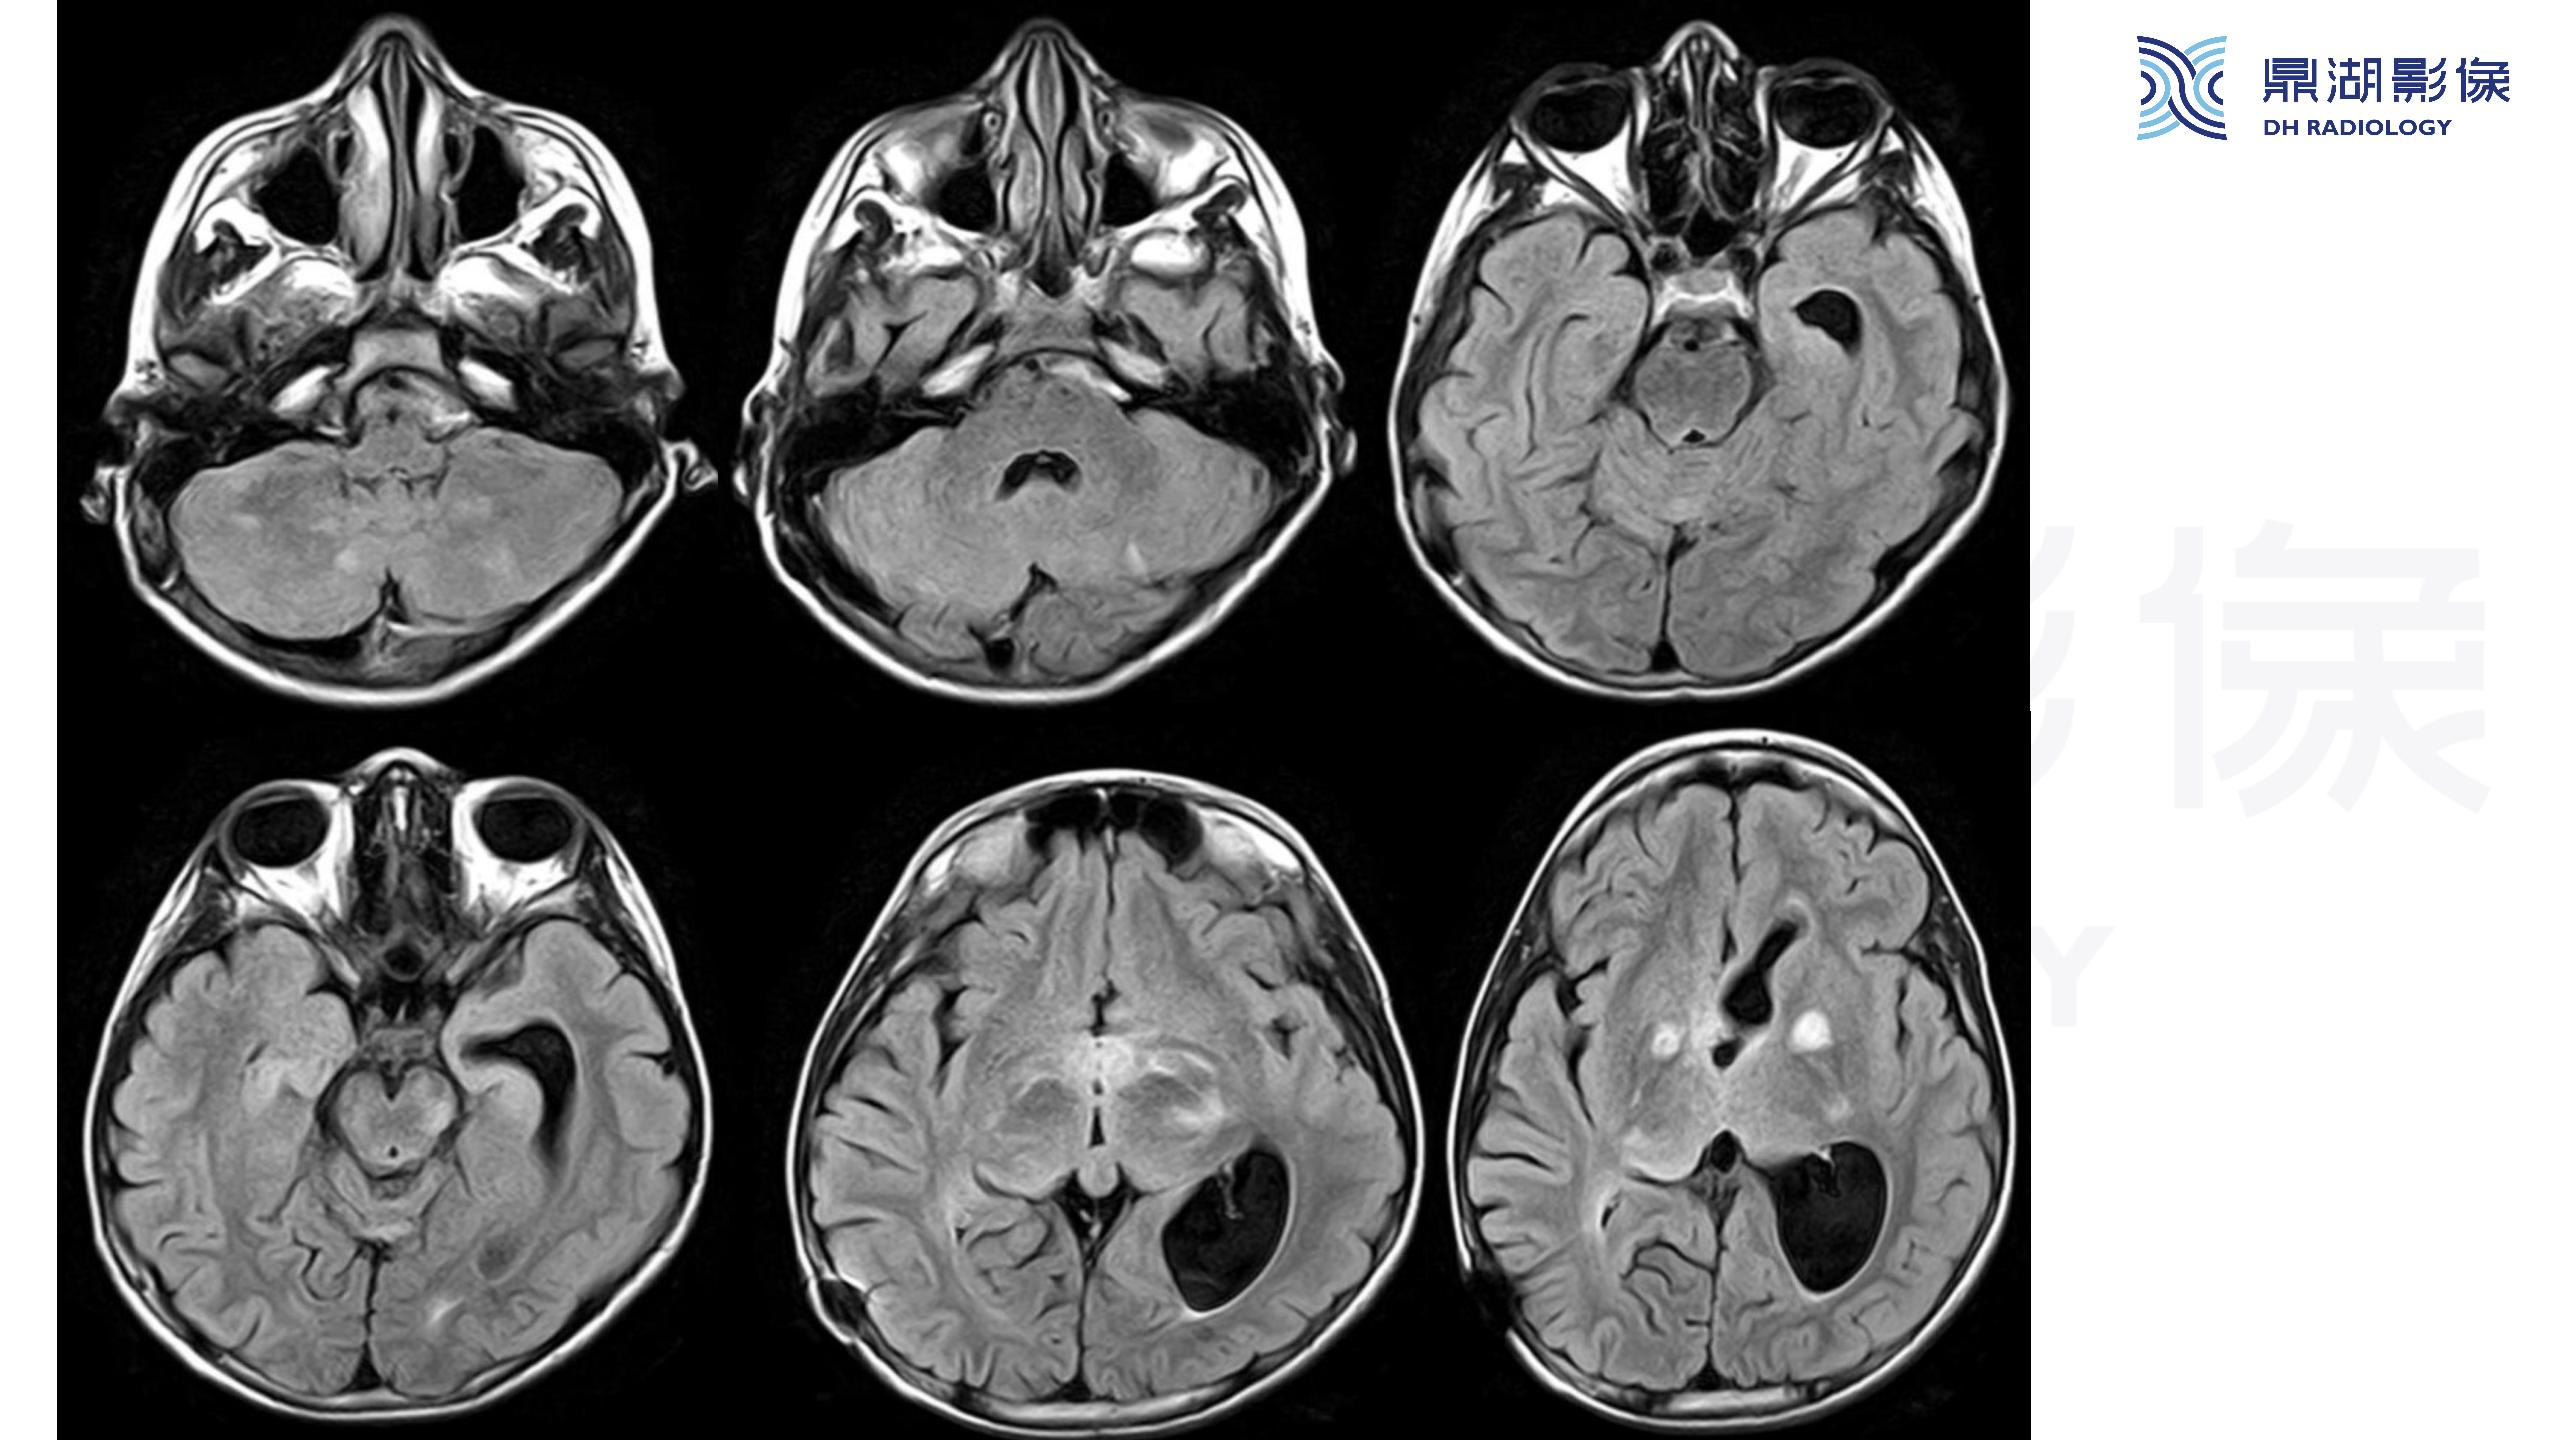

裂隙脑室综合征 (slit ventricle syndrome,SVS)-鼎湖社群读片病例